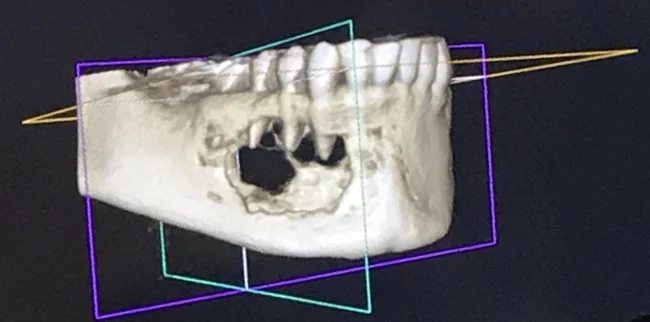

1. «В прошлом месяце я пришёл на чистку зубов к стоматологу. Я упомянул, что чувствую онемение в одном из зубов. Я был в ужасе, когда увидел опухоль, которая разрушает челюстную кость»